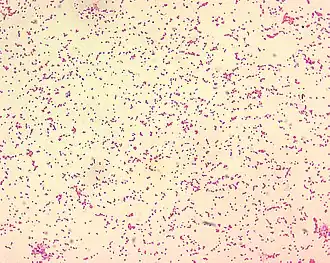

Патогенными для человека являются три представителя рода бруцелл: возбудитель бруцеллёза мелкого рогатого скота (Brucella melitensis), возбудитель бруцеллёза крупного рогатого скота (Brucella abortus) и возбудитель бруцеллёза свиней (Brucella suis)[4]. Есть описанные случаи заболевания бруцеллезом после контакта с штаммами Brucella canis.(эти случаи считаются редкими).[5] Бруцеллы очень мелкие, неподвижные, не образуют спор, но при определённых условиях могут образовывать капсулу. Характерен полиморфизм микробных клеток — в одном препарате можно встретить кокковые, овоидные и палочковидные формы. Они легко окрашиваются всеми анилиновыми красителями, грамотрицательны[6].